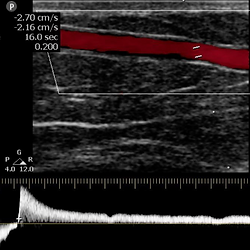

Venous Doppler ultrasound is a non-invasive diagnostic study that allows for the evaluation of venous circulation in the upper or lower limbs, analyzing the presence of thrombi, valvular insufficiency, and venous flow abnormalities using high-resolution ultrasound with color and spectral Doppler technology. This examination is the method of choice for diagnosing deep vein thrombosis (DVT) and for assessing varicose veins, venous reflux, or chronic circulatory problems, providing precise anatomical and functional information. During the study, the main veins of the lower limbs (femoral, popliteal, great and small saphenous, tibial, and peroneal) or upper limbs (subclavian, axillary, brachial, basilic, and cephalic) are analyzed. Venous compressibility, patency, flow direction, and valvular competence are evaluated, allowing for the identification of acute thrombi, recanalization, and pathological reflux. Most frequent clinical indications: Pain or swelling in arms or legs. Suspected deep vein thrombosis (DVT). Presence of varicose veins or heaviness in the legs. Discoloration or persistent edema. Pre- or post-venous surgery evaluation. Monitoring of treatments for venous insufficiency or thrombosis. Monitoring in patients with a history of DVT or risk factors (prolonged travel, immobilization, contraceptives, pregnancy, etc.). The study is safe, painless, and radiation-free. It provides essential information for the clinical and therapeutic management of venous diseases, preventing complications such as embolisms or varicose ulcers. Preparation: Fasting is not required. Comfortable clothing that allows for easy exposure of the limbs is recommended. 馃搷 Schedule your venous Doppler study to effectively prevent and treat your circulatory problems.